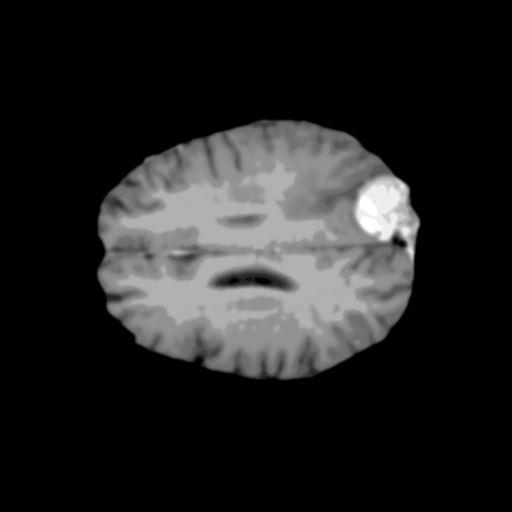

Extensive experiments have been performed in the current setup, and experimental outcomes are reported with the demonstration of numerical and statistical analyses using the proposed QFS-Net, QIS-Net [39], convolutional U-Net [18] and Residual U-Net (URes-Net) architectures [20]. The human expert segmented skull-tripped contrast enhanced DSC brain MR input image slices of size and ROIs are provided in Figure 5 as samples. The demonstration of QFS-Net segmented images followed by the essential post-processed outcome on the slice no. for class level with four distinct activation schemes () are shown in Figure 6. It is evident from the experimental data provided in Table LABEL:tab1 that the proposed QFS-Net performs optimally for the -connected quantum fuzzy pixel information heterogeneity assisted activation () with and gray scale set in comparison with other thresholding schemes and gray scale sets under the four evaluation parameters () [44]. The segmented tumors obtained using the proposed self-supervised procedure under class transition levels with four different thresholding schemes , , and are demonstrated in Figures 7- 8 for the class boundary sets and [39], respectively. The segmented images using the remaining two class boundary sets ( and ) [39] are provided in the supplementary materials section. The segmented ROIs describing the whole tumor region after the masking procedure using QIS-Net, U-Net and URes-Net are also reported in Figure 9.